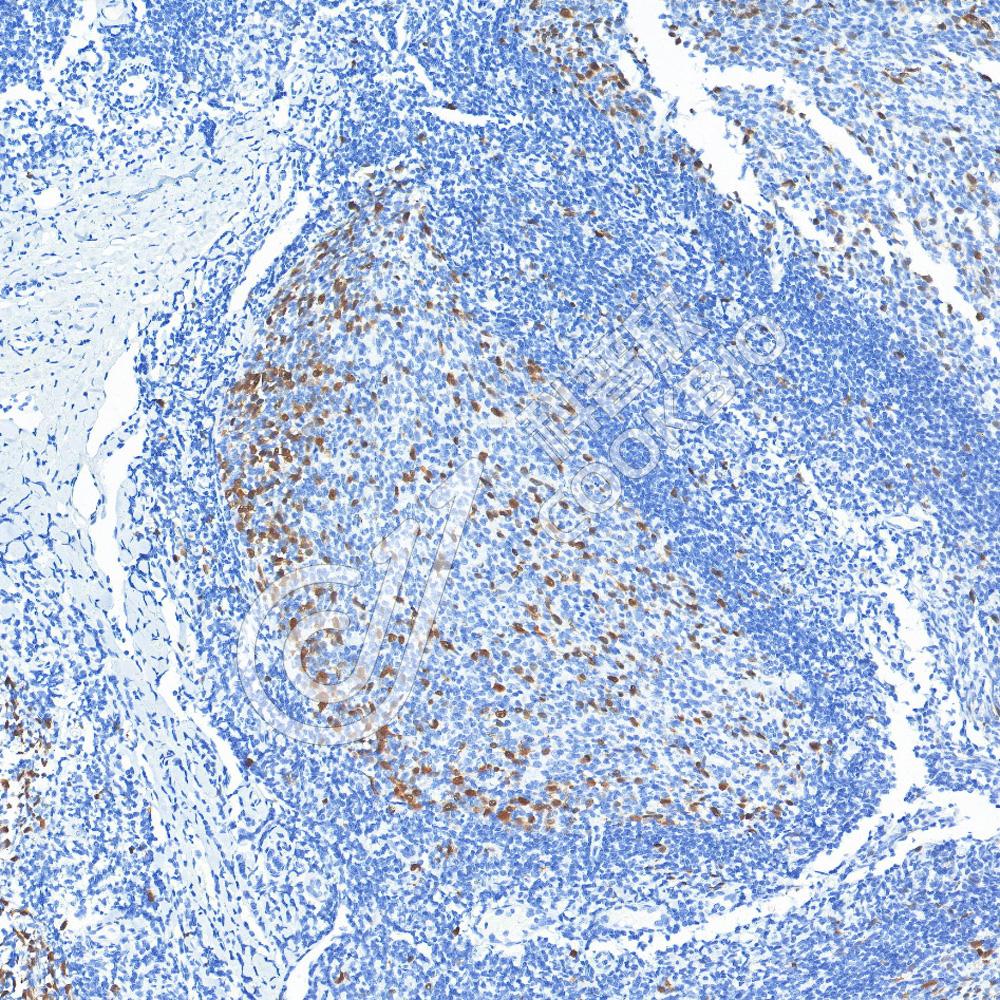

IHC检测Cyclin A2蛋白(货号 K2363684).

样品: 人扁桃体, 4%多聚甲醛 (货号KSG1101) 固定12-24小时.

抗原修复: 柠檬酸抗原修复液(干粉, pH 6.0) (KSG1201), 高压锅均匀喷气计时2分钟.

—抗: 1: 800稀释, 4℃ 孵育过夜.

二抗: S-vision免疫组化多聚二抗(山羊抗小鼠), 即用型(货号KB3903), 室温孵育20分钟.